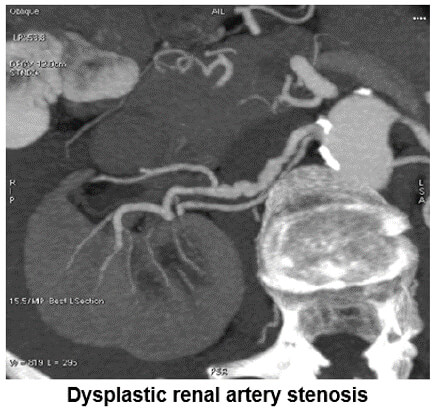

MIP Vascular: Renal Artery

This image shows us dysplastic renal artery stenosis. Notice the contour of the renal artery.

The image on the left shows us the facial nerve while the image on the right shows renal artery dysplastic stenosis.